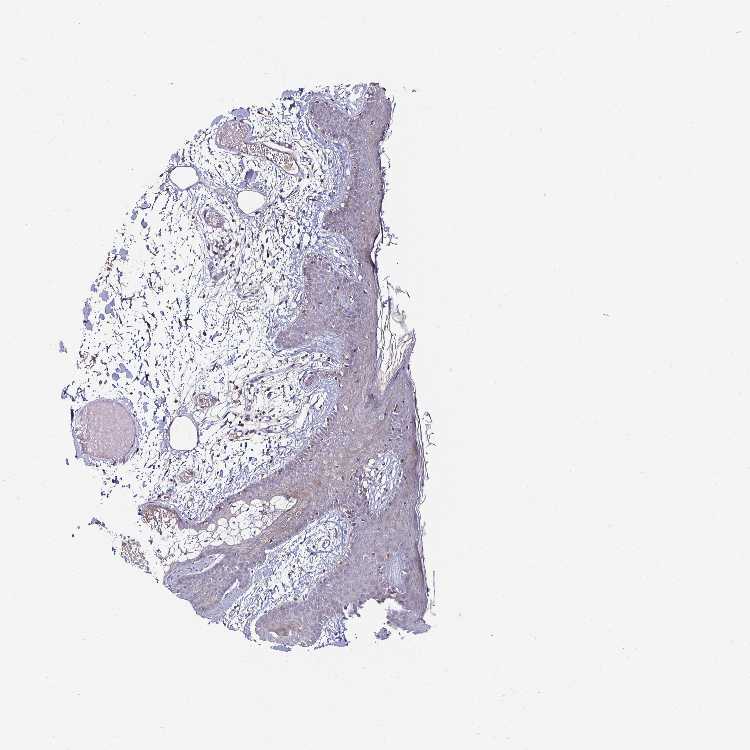

SKIN 2 - Antibody stainingi

Antibody staining in the annotated cell types in the current human tissue is reported as not detected, low, medium, or high, based on conventional immunohistochemistry profiling in selected tissues. This score is based on the combination of the staining intensity and fraction of stained cells.

Each image is clickable and will lead to virtual microscopy that enables deeper exploration of all samples and also displays staining intensity scores, fraction scores and subcellular localization as well as patient and tissue information for each sample.

Antibody HPA054846Antibody CAB021982

Epidermal cells MediumNot detected